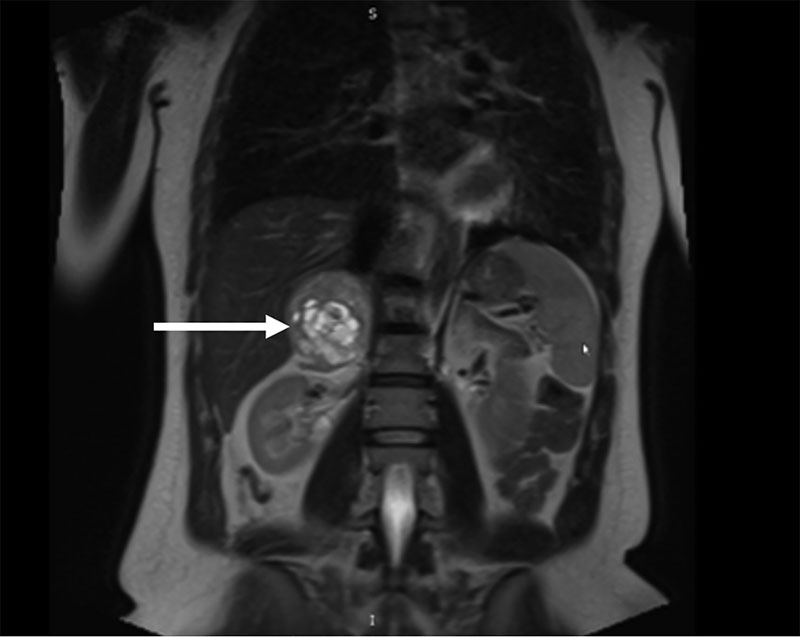

Рис. 2. Образование правого надпочечника на компьютерной томограмме во фронтальной плоскости, указано стрелкой

По данным магнитно-резонансной томографии (МРТ) ОБП и забрюшинного пространства от 10.12.2024 г.: правая почка оттеснена книзу неоднородным отграниченным образованием, локализованным вдоль внутренней ножки правого надпочечника, округлой формы, размерами 5,8 × 6,2 × 5,3 см; в центре жидкостный компонент, окруженный по контуру стромой с диффузным типом накопления контрастного препарата; левый надпочечник Y-образной формы, толщина ножек до 5 мм, без дополнительных образований.

Заключение: МР-томографические признаки кистозно-солидного образования правого надпочечника; микрокисты печени; конкремент в желчном пузыре, хронический холецистит; минимальный двусторонний гидроторакс.

По данным компьютерной томографии (КТ) ОБП и забрюшинного пространства от 11.12.2024 г.: надпочечники – левый Y-образной формы, образований не выявлено; правый содержит образование, неравномерно накапливающее контрастное вещество, 63 × 53 мм. После внутривенного усиления накопление контрастного вещества в нативную, артериальную, венозную, отсроченную фазы составляло 29/56/52/47 HU (единиц по шкале Хаунсфилда) соответственно.

Заключение: КТ-признаки кистозно-солидного образования правого надпочечника, мелких кист печени, желчнокаменной болезни (ЖКБ), хронического холецистита; двусторонний минимальный гидроторакс (рис. 1, 2).